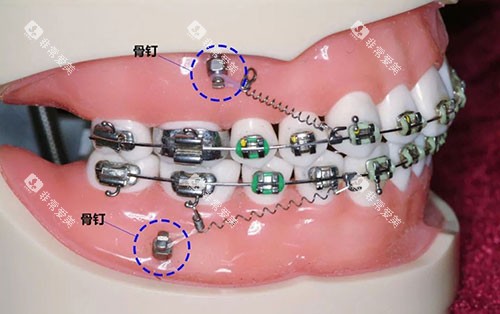

(一)传统金属托槽矫正

价格区间:8000 - 15000 元

项目介绍:价格较为实惠,是经济型矫正方式,但美观度相对较低。

(二)自锁托槽矫正

价格区间:10000 - 20000 元

项目介绍:相比传统托槽,舒适度和矫正效率更高,复诊间隔时间更长。